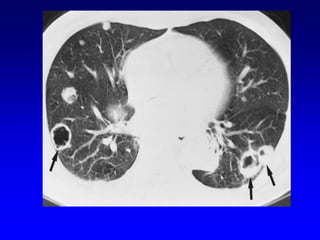

Multiple cavities:

1. Aspiration.

2. TB

3. Fungal.

4. Metastatic.

5. Septic emboli.

6.Wegners granulomatosis